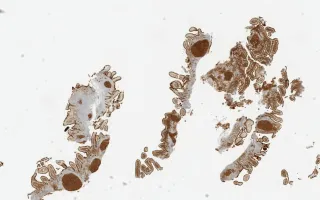

Duodenum, Follicular lymphoma, CD10 stain

Similar to nodal FL, most GI FLs are positive for CD20, CD79a, CD10, BCL-6 and BCL-2. What is unique about duodenal FLs is the presence of the “hollow” pattern of staining seen with CD21 and CD23. This is due to the peripheral arrangement of the follicular dendritic cells with relative sparing of the follicular centre. In contrast, the follicular dendritic cells are scattered throughout the neoplastic follicles in nodal FL.

This slide shows CD10 stain. See Related Content for H&E, CD20, BCL6, BCL2, and CD23 stains.